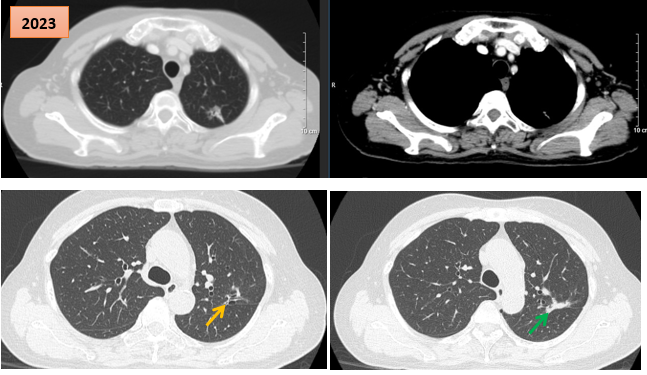

Hình ảnh cắt lớp vi tính theo dõi trong quá trình điều trị, tổn thương xơ hóa tại vị trí u cũ (mũi tên xanh) và giãn khu trú các nhánh phế quản liền kề (mũi tên vàng)

Bệnh nhân tiếp tục được theo dõi và điều trị duy trì bằng erlotinib. Đến thời điểm đánh giá lại vào tháng 5/2023, sau 6 năm điều trị liên tục, bệnh nhân vẫn trong tình trạng ổn định: Không đau ngực, không khó thở, các chỉ điểm khối u CEA và Cyfra 21-1 duy trì trong giới hạn bình thường.

Kết quả chụp CT ngực - bụng và cộng hưởng từ sọ não không ghi nhận thêm tổn thương mới. Tại vị trí u cũ, tổn thương xơ hóa gây co kéo rãnh liên thùy và giãn khu trú các nhánh phế quản lân cận, song không ảnh hưởng đến chức năng hô hấp và không gây triệu chứng lâm sàng.